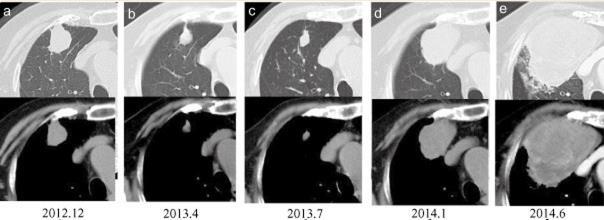

女性,85岁,吸烟史。

2012年12月体检发现2.8cm肺结节(图1a)。

2013 年 4 月肿瘤阴影的大小从2.8cm减小到1.8cm(图1b)。

强烈怀疑肿瘤是良性,密切影像学随访。肿瘤阴影在接下来的三个月内保持不变(图1c)。2013年7月,患者被确诊为类风湿关节炎,开始接受糖皮质激素治疗。

2014 年 1 月,肿瘤从1.8cm增加到4.8cm(图1d)。

诊断结果:肺大细胞神经内分泌癌